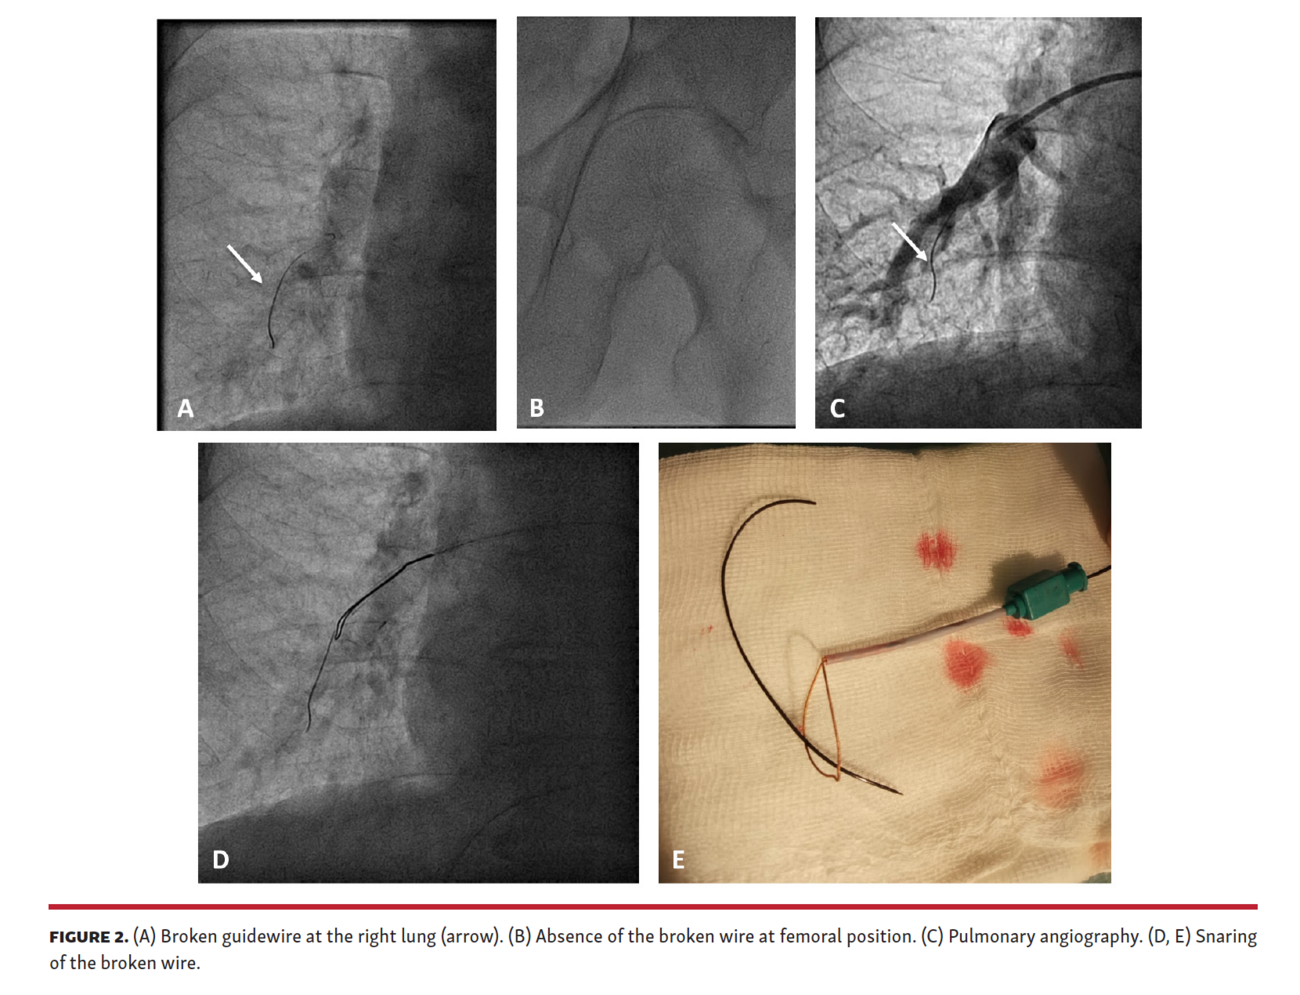

Migration of a Broken Rotawire Across the Aorta During Retrieval Using

Migration of a Broken Rotawire Across the Aorta During Retrieval Using Guide Wire Broken Guidewire fracture could be due to entrapment. We describe a case of a. guidewire fracture could be due to (a) entrapment into or behind stent struts,. We also report a simple yet. we report a case of a broken guidewire during intramedullary nail fixation of a proximal femur fracture with subtrochanteric extension. guidewire fracture is a rare. Guide Wire Broken.